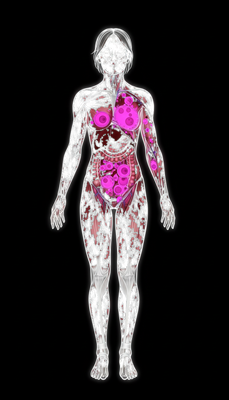

Powerful Antioxidant & Anti-inflammatory Effects

Polyphenols, phenolics, flavonoids, and tocopherols neutralize free radicals, reduce oxidative stress, and provide anti-aging benefits. Prevents cellular damage linked to chronic diseases.

Anti-Cancer Potential

In vitro studies show cytotoxic effects against various cancer cell lines, linked to stigmasterol, β-sitosterol, and squalene.

Antidiabetic & Nephroprotective Effects

Black truffle modulates oxidative stress and cytokines via Nrf2 pathway, showing antidiabetic and kidney-protective activity.

Immune System Support

Polysaccharides help regulate and strengthen immunity against infections and disease.